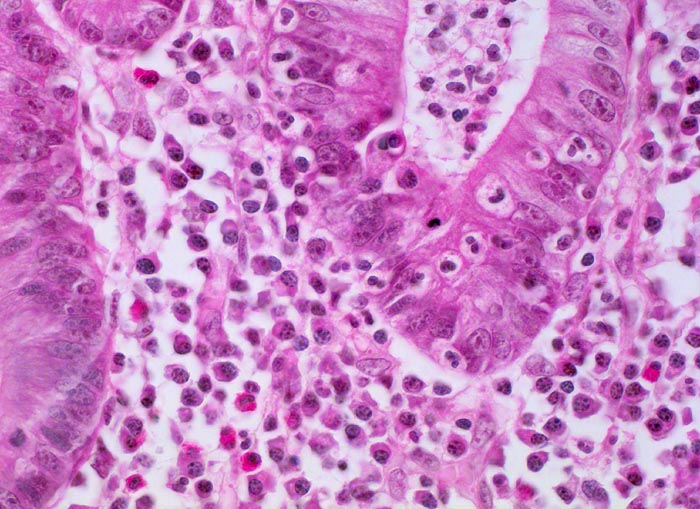

PathoPic – image database / PathoPic ID 5080 - Colitis ulcerosa: Kryptitis

Colitis ulcerosa: Kryptitis

Neutrophile Granulozyten infiltrieren das Kryptenepithel (=Kryptitis). Verdichtetes Entzündungsinfiltrat in der Lamina propria bestehend aus zahlreichen Plasmazellen mit exzentrisch gelagerten Kernen, neutrophilen Granulozyten und eosinophilen Granulozyten. Die Krypte enthält zusätzlich einen Kryptenabszess. Das Kryptenepithel zeigt eine deutlich reduzierte Schleimbildung, das Zytoplasma der Epithelzellen ist basophil und die Kerne zeigen reaktive Atypien (Vergrösserung und Abrundung des Kerns, Hyperchromasie, grosse Nukleolen).

Kolektomie wegen chronischer therapierefraktärer Kolitis.

400